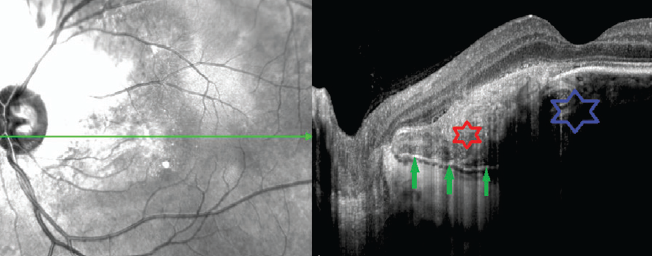

OCT investigations revealed a local elevation of the retinal profile. A thickening of the retinal inner layers was primarily identified at the edges of the lesion and at the nerve fibers layer. On the other hand, large cavities with uneven sharp contours and an intensely hyperreflective wall were noticed in the center of the focus, represented by mulberry-shaped patterns. Multiple hyperreflective inclusions were also found inside the cavities. The choroid thickness in the focal zone did not differ from the adjacent zone, however, it was impossible to evaluate its structure as a result of partial screening and the manifestation of artifacts (Fig. 15), similar to the reverberation effect in US.

Fig. 15. Optical coherence tomography - horizontal scan across the maximal prominence of retinal astrocytoma. Asterix – a cavity in the center of the focus; red arrows – thickening of the inner layers of the retina along the edges of the focus; green arrows – zone of partial shielding of underlying structures

Рис. 15. Оптическая когерентная томография — горизонтальный срез через зону максимальной проминенции астроцитомы сетчатки. Звёздочка — полость в центральной части очага; красные стрелки — утолщение внутренних слоёв сетчатки по краям очага; зелёные стрелки — зона частичного экранирования подлежащих структур

The OCT presentation, together with the respective ophthalmoscopic findings, facilitated the diagnosis of RA in these patients.

Finally, and as opposed to the diseases described above, the pathological process of RA tends to localize in the retinal inner layers. Despite the fact that the choroid remains intact, its visualization is significantly complicated because of pronounced retinal changes (involving a thickening of the retinal inner layers, the presence of large cavities with uneven clear contours and intensely hyperreflective wall, and multiple hyperreflective inclusions), that can, in turn, block the signal stemming from the underlying tissues.